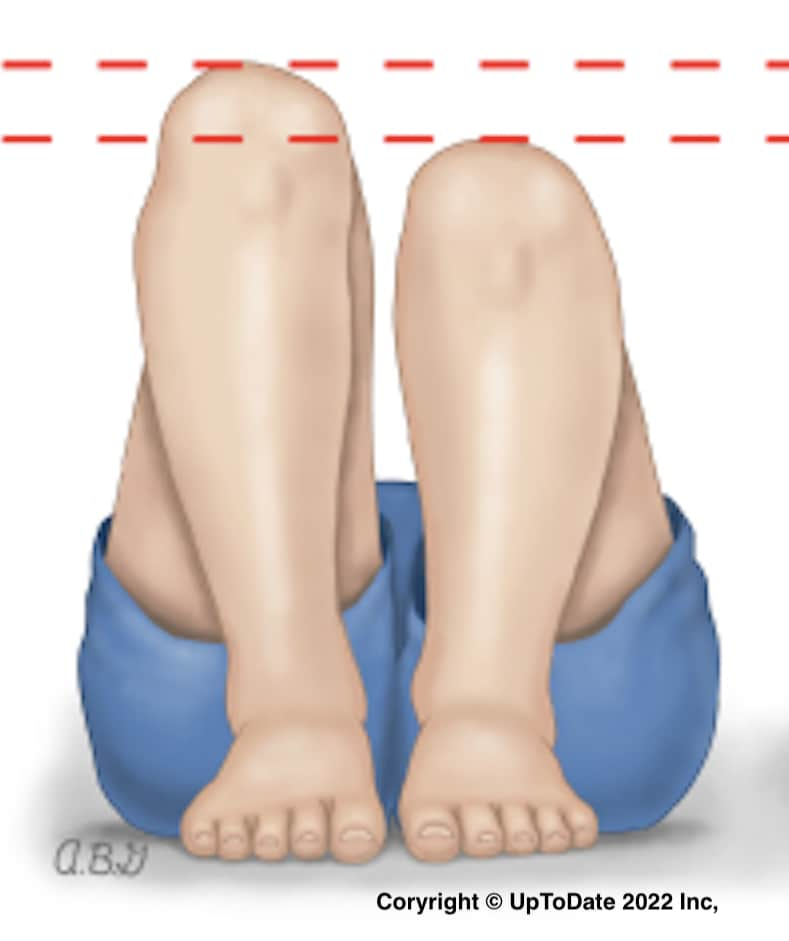

③ 脚の長さ(下肢長差)

脱臼した側の脚が少し短くなるのを利用した方法です。仰向けで脚を立て、足底を平らに並べて、かかとをお尻にくっつけます。その時の膝の高さを比べます。差があれば低い方に脱臼の疑いがあります。軽い脱臼ではわからない場合がありますが、差があれば強く脱臼を疑う所見です。ただし、左右差をみる検査なので、両側の脱臼はこの方法ではわかりません。

脱臼した側の脚が少し短くなるのを利用した方法です。仰向けで脚を立て、足底を平らに並べて、かかとをお尻にくっつけます。その時の膝の高さを比べます。差があれば低い方に脱臼の疑いがあります。軽い脱臼ではわからない場合がありますが、差があれば強く脱臼を疑う所見です。ただし、左右差をみる検査なので、両側の脱臼はこの方法ではわかりません。